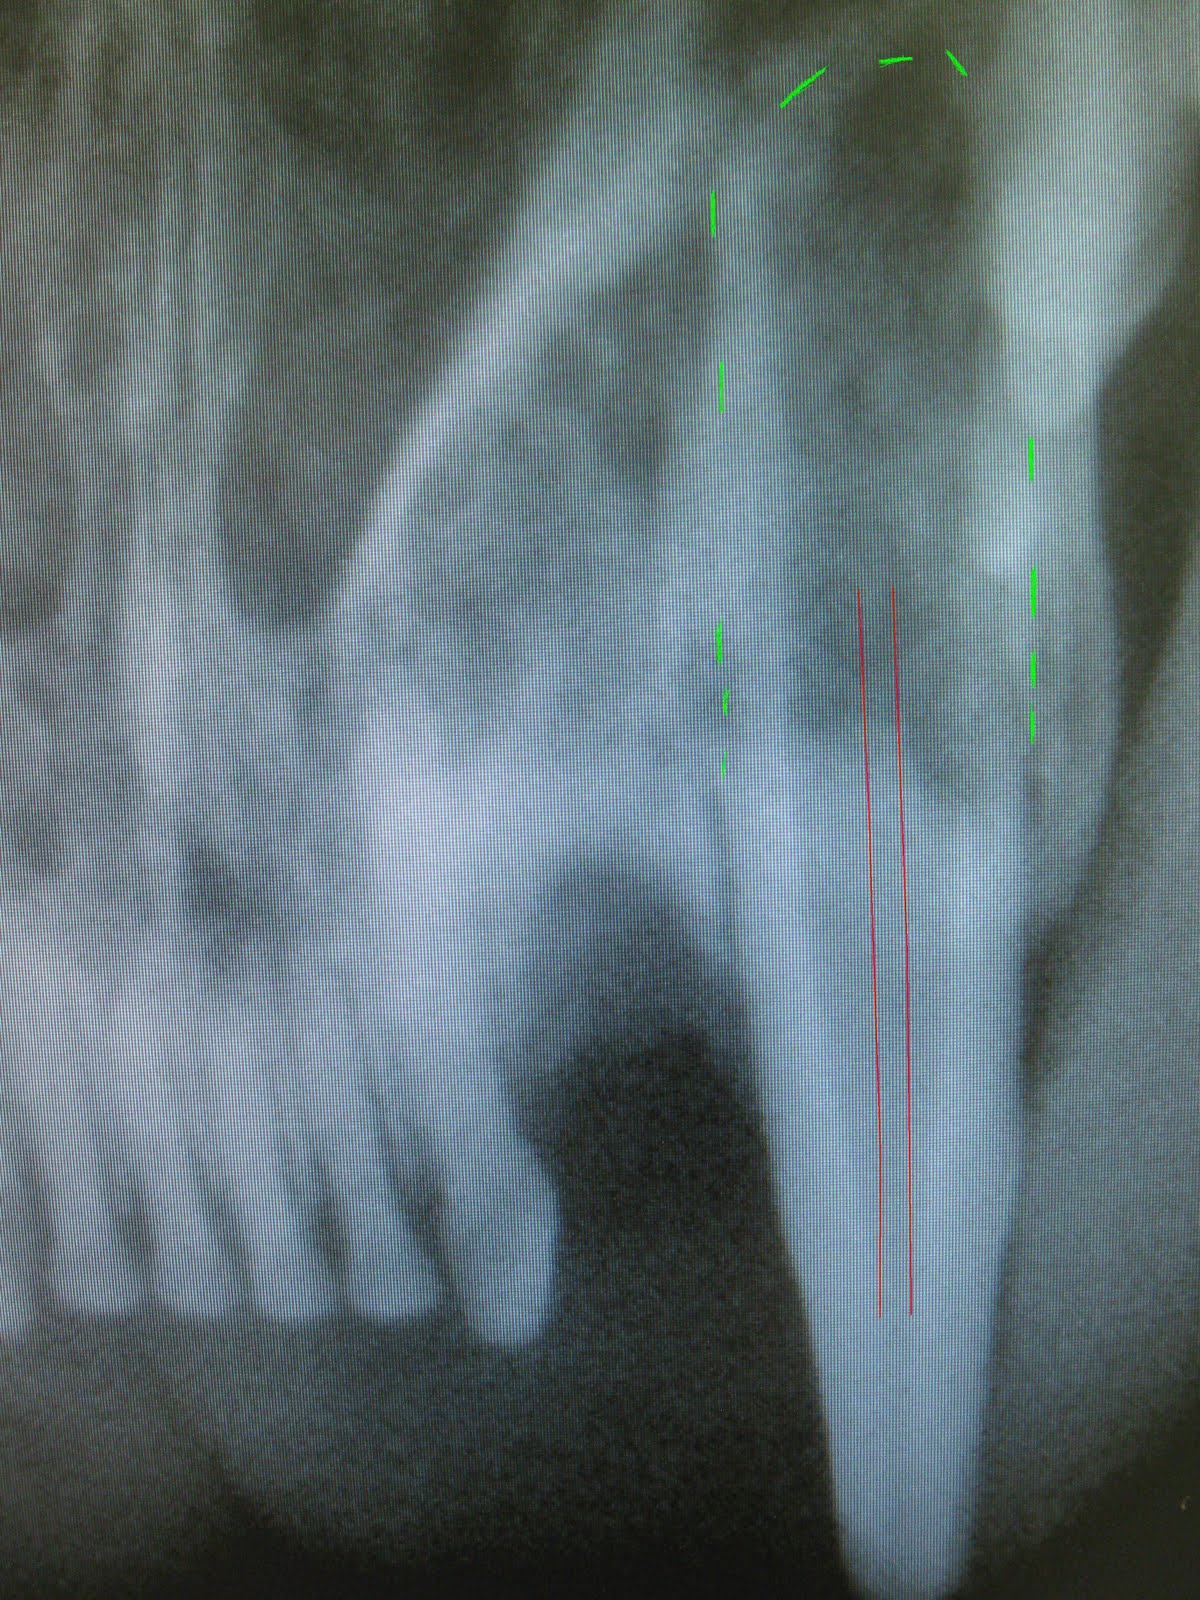

Before removing teeth, I almost always take a radiograph. I want to see what shape the roots and bones are in. I was more than a little confused when I saw the radiograph for this tooth. Normally, the pulp of a mature cat or dog becomes a very narrow. The pulp on this one got so large the root basically disappeared.

Picture: the red line represents where the pulp should be and the green lines represent where the tooth root should be.